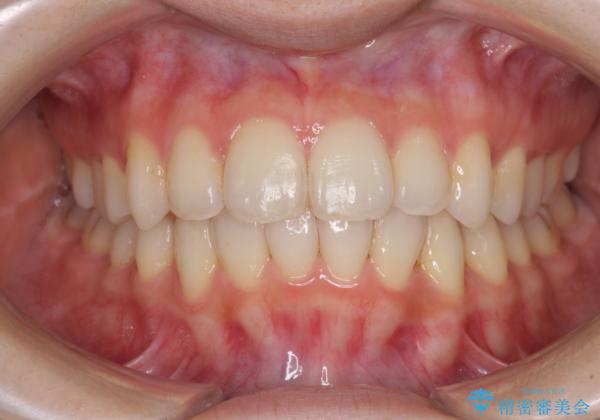

インビザラインを用いた非抜歯矯正

- 1年11ヶ月

- 前歯のデコボコを気にして来院された患者様です。

叢生と捻転が随所に認められるものの、マウスピースで十分対応可能であったため、インビザラインにて矯正治療を行うこととしました。

マウスピース矯正は毎日しっかりと装着することがとても大切です。

こちらの方はしっかりと指示を守って装着してくださったため、予定通り治療を終えることができました。